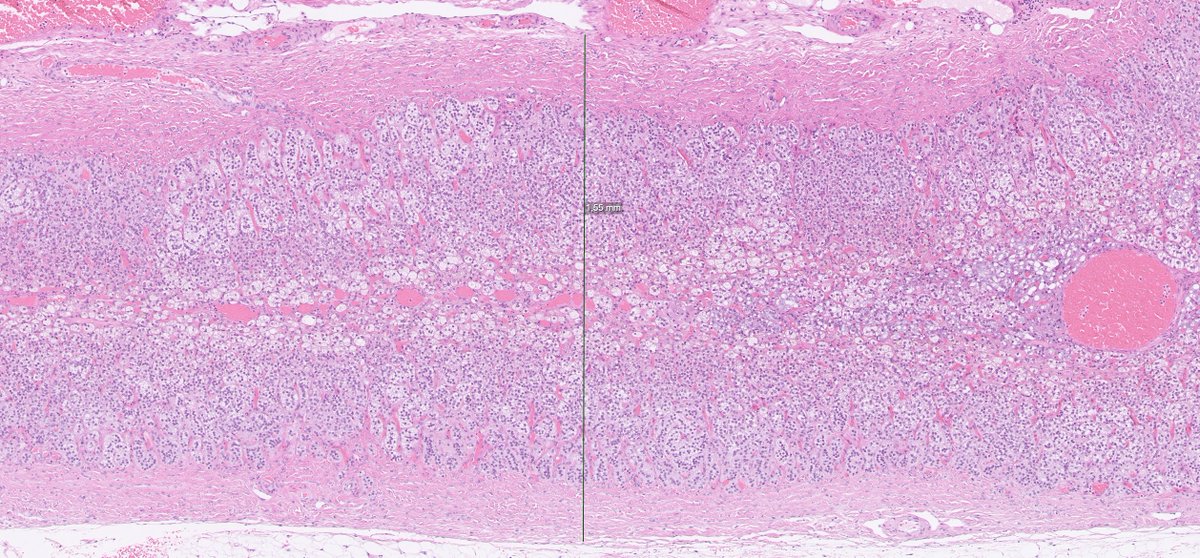

70ish y/o male, gastric lesion, excision. Tumor is locaded in the submucosa, with infiltrative growth to the subserosal layer. Cells are arranged in solid sheets. Monomorphic appearance. Let's have a closer look! Follow the thread... 🧵

DrJuhlin's tweet image. 70ish y/o male, gastric lesion, excision. Tumor is locaded in the submucosa, with infiltrative growth to the subserosal layer. Cells are arranged in solid sheets. Monomorphic appearance. Let&apos;s have a closer look! Follow the thread... 🧵